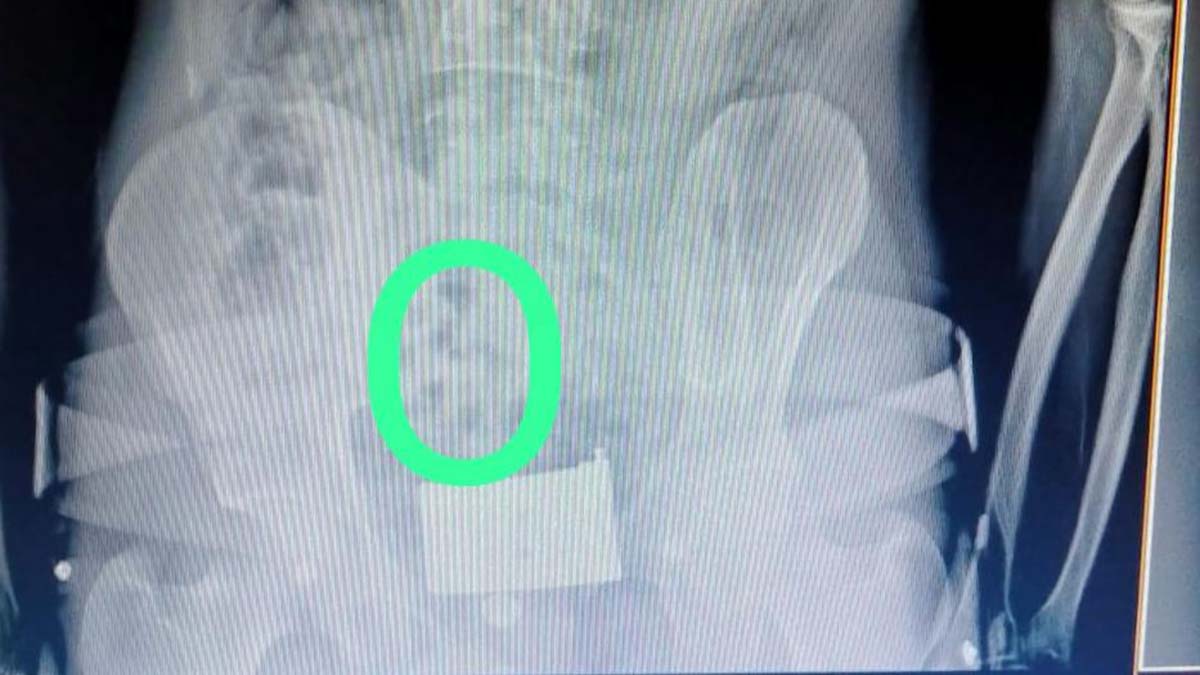

İl Emniyet Müdürlüğü Narkotik Suçlarla Mücadele Şube Müdürlüğü ekipleri, Erzincan- Erzurum yolunda aracı durdurdu. Polis, İran’dan Türkiye’ye giriş yapan araçtaki 2 kişiden şüphelenince muayene için hastaneye götürdü ve röntgen çekildi.

İran uyruklu kişilerin midesinde kapsüller olduğu görüldü. Hastanede yapılan işlem sonrası 2 şüphelinin midesinden 64 kapsül halinde 558,83 gram eroin çıkarıldı. Emniyetteki sorguları tamamlanan Ali F. ile Saman G., sevk edildiği adliyede çıkarıldığı hakimlikçe tutuklandı.